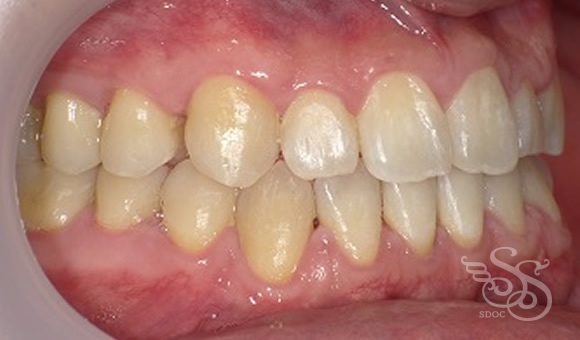

左側:術前

左側:術後